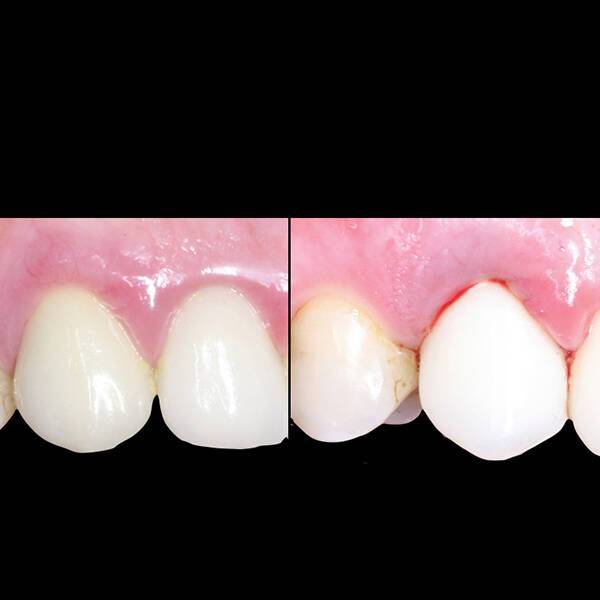

- Fixação da Prótese: Em até 72 horas após a cirurgia, a prótese provisória é instalada, permitindo que o paciente recupere a funcionalidade e a estética imediatamente.

- Conforto e Estética: A prótese provisória é funcional e visualmente semelhante aos dentes naturais.

- Melhora da autoestima: O impacto positivo de um sorriso completo é imediato, melhorando a qualidade de vida.